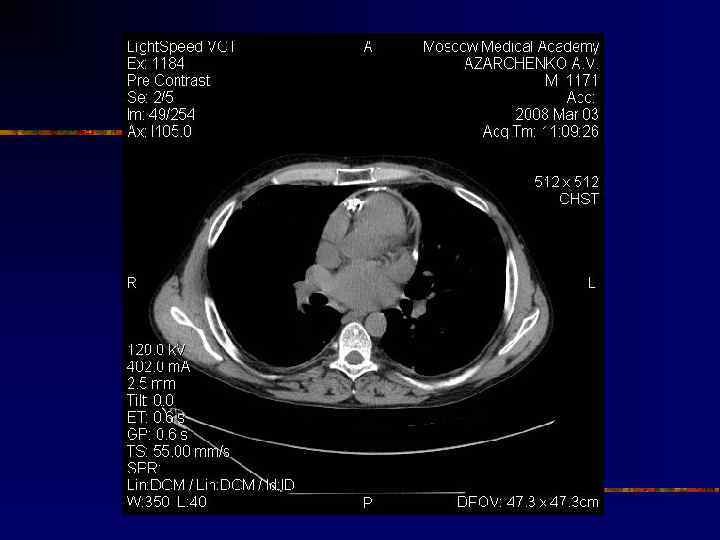

Кальциноз перикарда